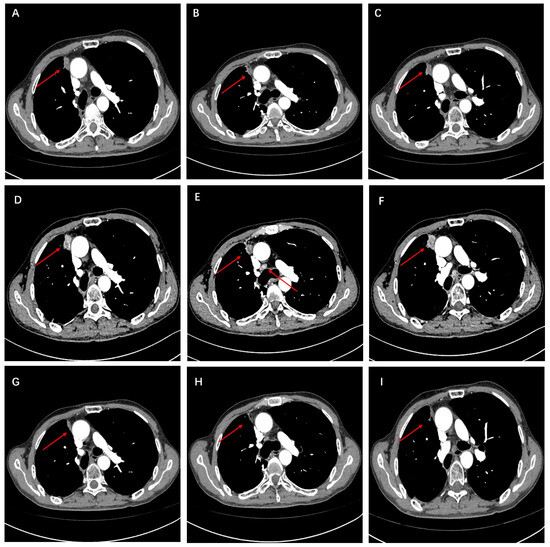

Mutation profiling of ctDNA from peripheral plasma collected one week after surgery and DNA obtained from formalin-fixed paraffin-embedded (FFPE) tumor tissue sections was performed using next-generation sequencing (NGS). The NGS tests, which utilized the LungTrak panel, targeted 139 lung cancer-related genes and were conducted at a centralized, CLIA-certified, and CAP-accredited clinical testing center (Nanjing Geneseeq Technology Inc., Nanjing, China). The sequencing platform used for the study was Illumina. A rare KIF13A-RET fusion involving exon 19 of KIF13A and exon 12 of RET was detected in tumor tissue (Figure 2). Mutations in the TP53, APC and MYC genes were also detected in the tissue sample. CtDNA was not identified in the peripheral plasma one week after surgery. Considering the patient’s long history of smoking and tumor staging, postoperative therapy was recommended. However, the patient declined adjuvant chemotherapy. After further discussion and collaborative decision-making, the patient was started on oral pralsetinib at a dose of 400 mg/d on postoperative day 84. One month after starting the medication, the patient experienced adverse reactions such as fatigue and loss of appetite, prompting a dose adjustment of pralsetinib to 300 mg/d. Upon the patient’s request, ctDNA was monitored at periodic intervals using LungTrak ctDNA testing. The patient’s ctDNA levels, measured using the assay above-mentioned, 7 and 206 days after surgery, were both 0.0% mutation allele frequency (MAF), with repeat ctDNA analysis 12 months after taking pralsetinib indicating persistently negative ctDNA at 0.0% MAF. Due to personal compliance issues, the patient became irregular in taking medication after one year of adherence. In Feburary 2023, after 20 months on pralsetinib therapy, ctDNA assessment identified detectable KIF13A-RET fusion 0.1% MAF. The finding in ctDNA level prompted a chest and upper abdominal enhanced CT scan, which did not reveal any signs of recurrence or metastasis. After 1 month of regular pralsetinib intake, ctDNA test no longer detected the RET fusion. However, repeat CT imaging 3 months later revealed a single nodule in the right pleura, suggesting possible metastasis (Figure 3A–C). On 27 August 2023, ctDNA analysis identified detectable KIF13A-RET fusion 0.2% MAF again. Subsequent restaging imaging revealed growth in the right pleura nodules 3 month prior, and new enlargements were observed in the N4R and N7 nodes, consistent with disease progression (Figure 3D–F). In November 2023, two months after treatment with bevacizumab in conjunction with the original regimen, a follow-up chest CT scan revealed a reduction in both the pleural metastatic lesion and mediastinal lymph nodes compared to previous imaging (Figure 3G–I). Longitudinal ctDNA levels monitoring indicated a clearance to 0.0% MAF in December 2023, consistent with radiological changes. The results of dynamic monitoring of ctDNA during the treatment process are presented in Figure 4.

Figure 3.

(A–C) At 27 months post-surgery, a follow-up chest-enhanced CT revealed nodules indicative of pleural metastasis on the right side. (D–F) After three months of continued treatment with the original regimen following recurrence, a follow-up CT scan revealed pleural metastatic lesions and enlarged mediastinal lymph nodes. (G–I) After three months of adding bevacizumab to the original regimen, a follow-up CT scan revealed a reduction in pleural metastatic lesions and shrinkage of mediastinal lymph nodes.